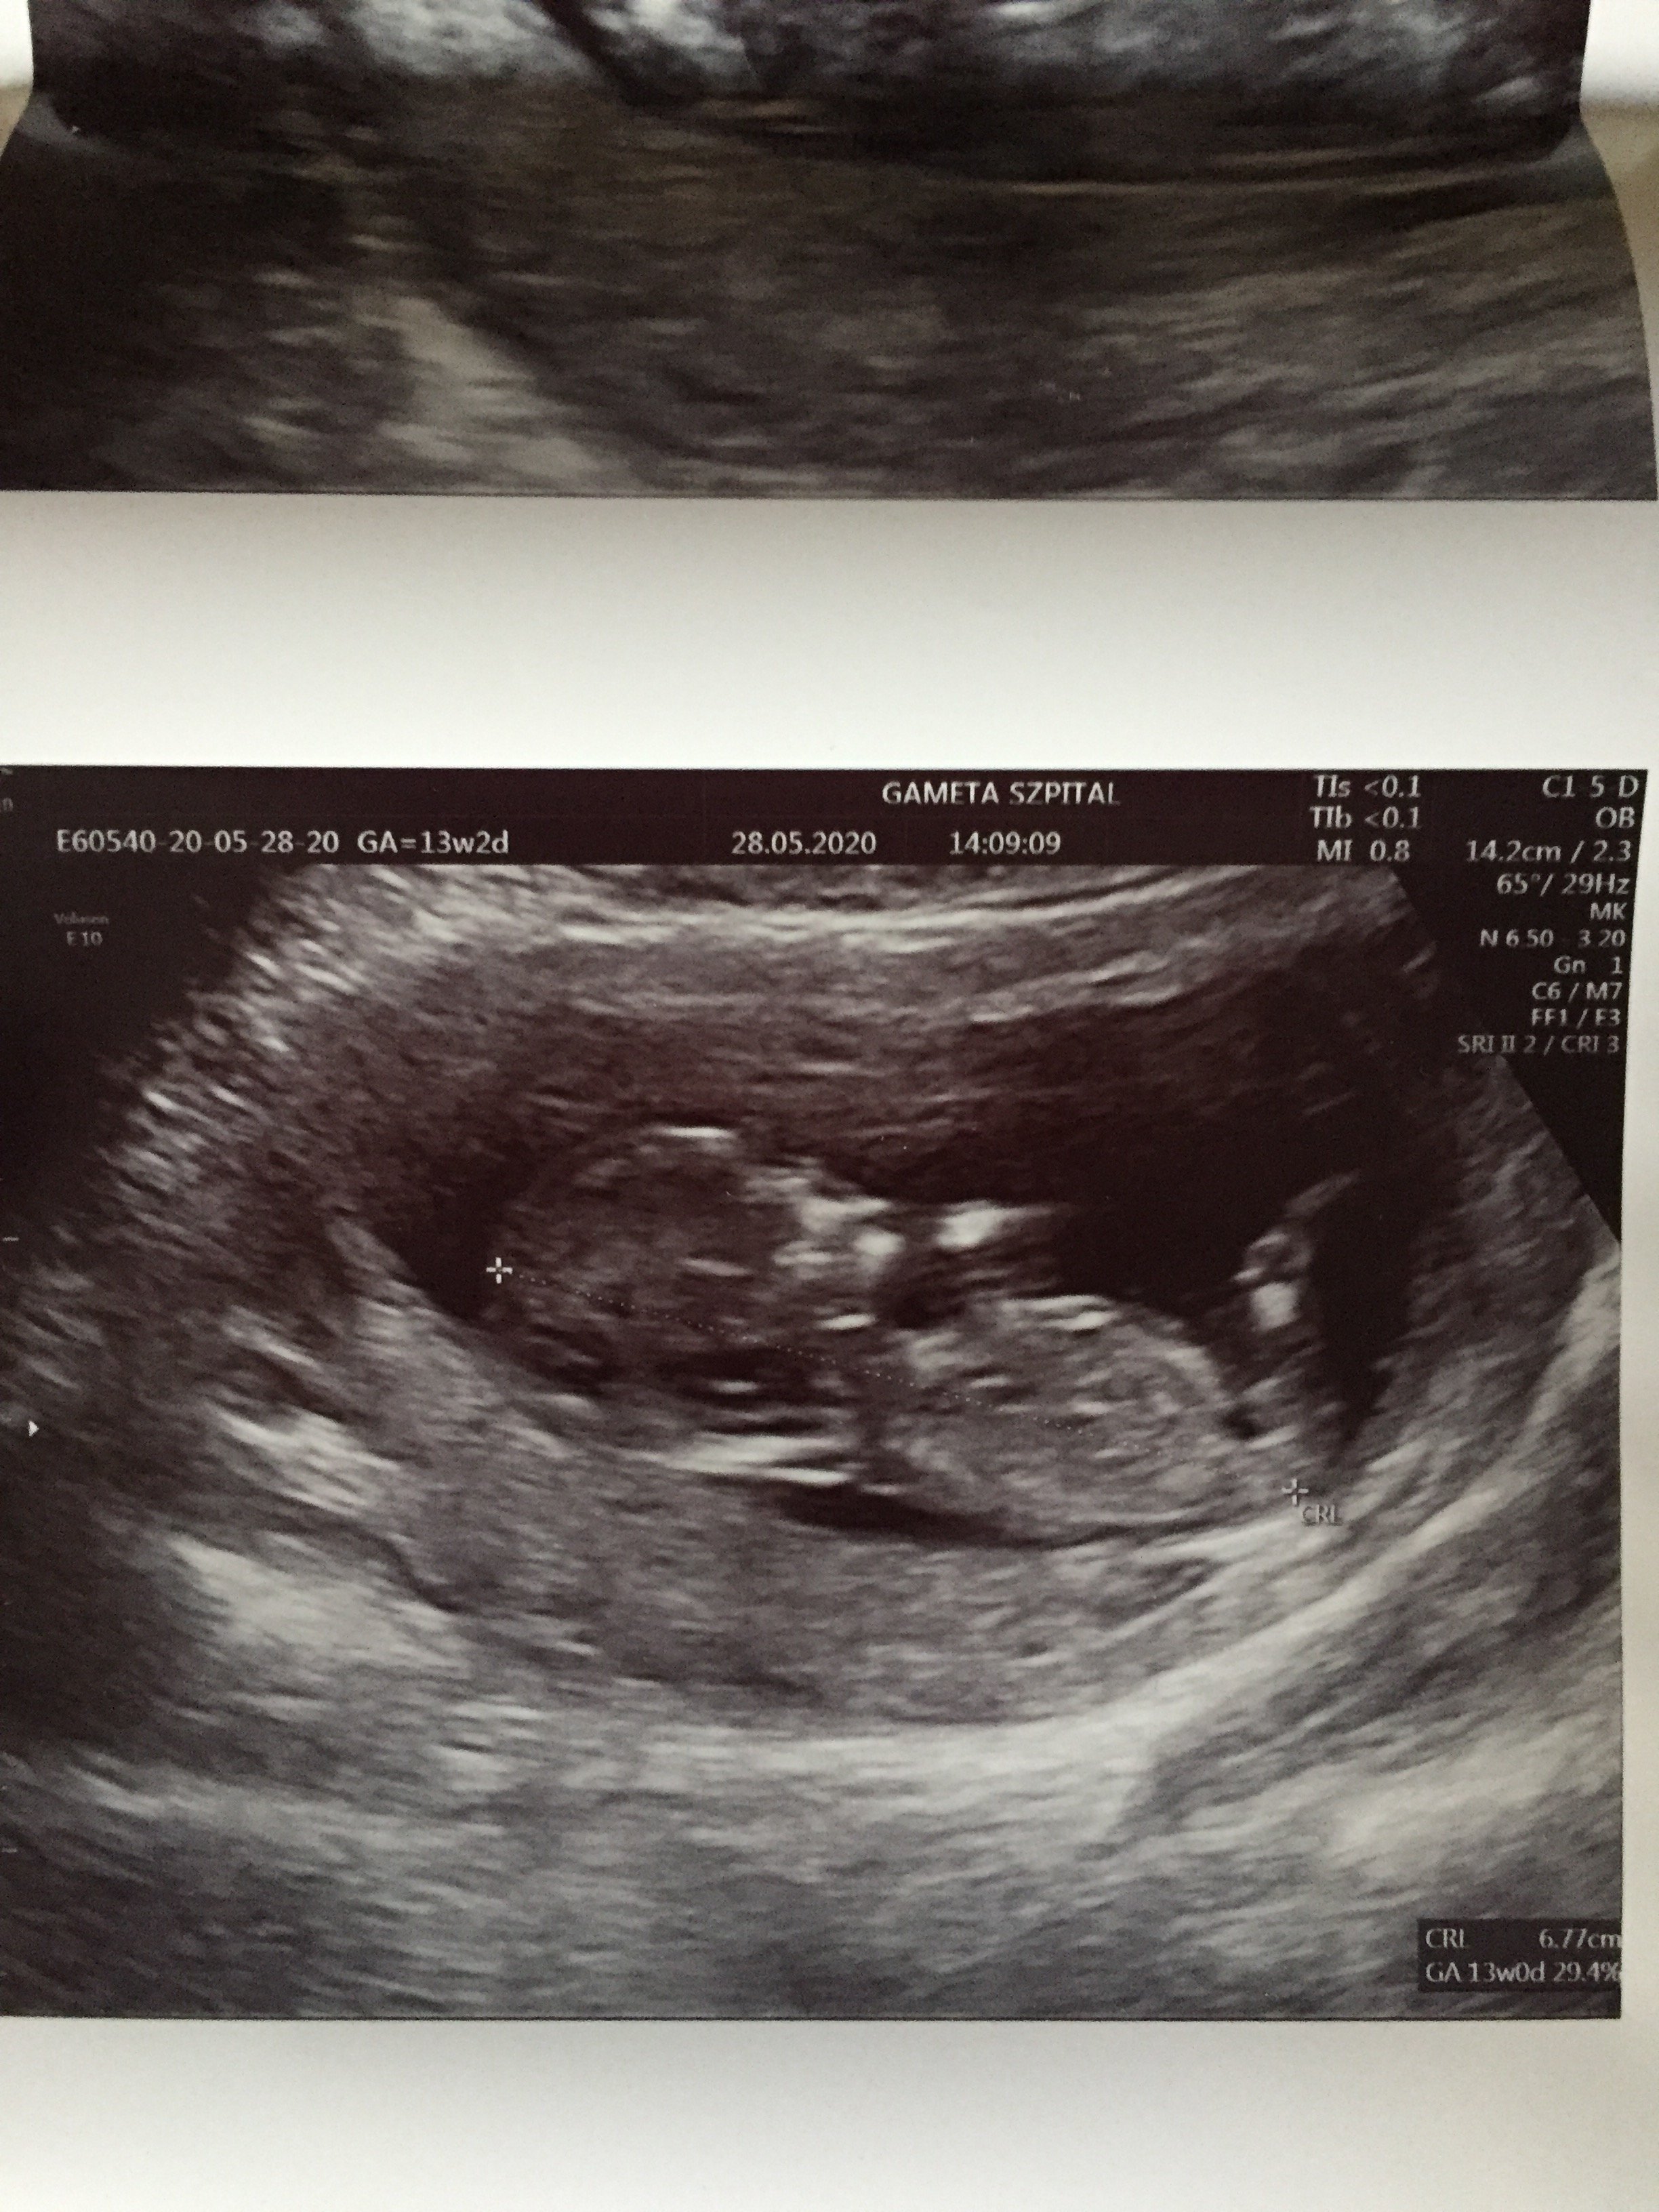

Pięknie, serdeczne gratulacjeNo i ja się w końcu pochwale moja kruszynka ❤ Mamy prawie 7 cm (6,8) dziś 13 równy tydzień wiec jutro wkraczamy w 14 wowwszystko prawidłowo na usg prenatalnym żadnych uwag zdrowa dzidzia. Najważniejsze, ze krwiak się całkowicie wchłonął juuupi nie ma po nim śladu

mąż nie mógł wejść ze mną niestety ale całe usg dostałam na pendrivie wiec widzieli już rodzice no i mąż również cudowny filmik jak wszystko mierzył lekarz i jak cudownie podskakiwała i kopała bo.... prawdodpobnie dziewczynka

Dziś miałam prenatalne i w usg wszystko dobrze,Na razie mam wynik tylko z samego usg i jest 1:4xxx, z pappa bede miala wynik w przyszłym tygodniu. Ciekawe jak sie zmieni.

A jakie miałaś CRL do tego NT?Dziś miałam prenatalne i w usg wszystko dobrze,

Nt: 1,3mm

Kość nosowa widoczna

przepływy też ok

A ryzyko 21 podstawowe 1:533

Skorygowane1:762

Pappa z krwi wyszła mi trochę nisko

I tak się trochę martwię....